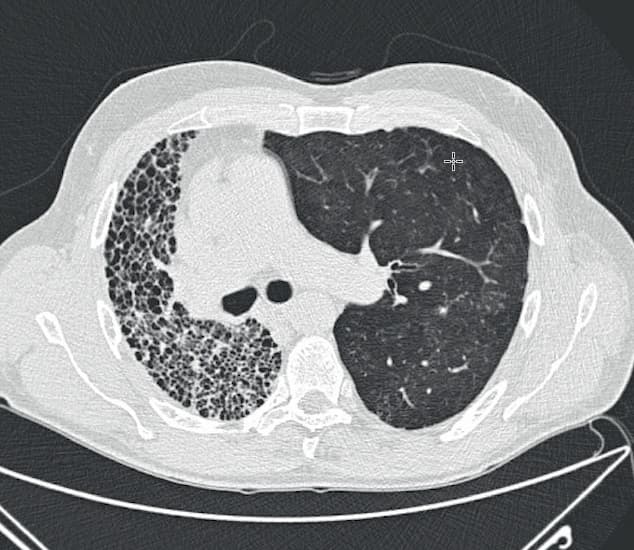

©. Enkeltlungetransplanteret patient med idiopatisk pulmonal fibrose. Til venstre ses den native lunge.